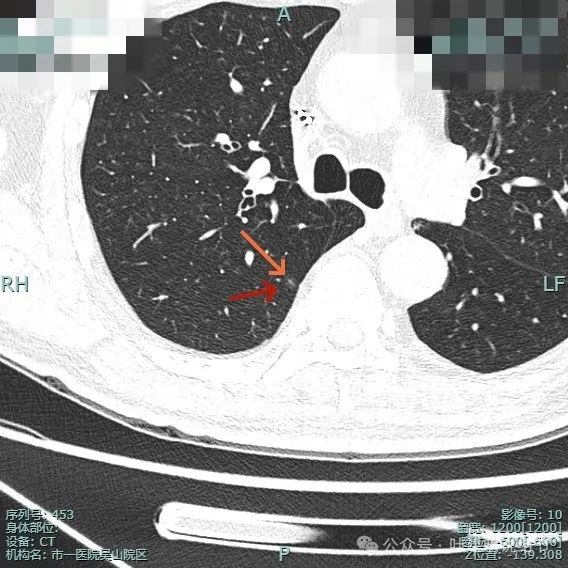

左下背段病灶实性,密度较高,紫色箭头处表面有细锯齿状,桔色箭头示有血管发出分支进入病灶且进入的血管到了结节边上有增粗。

多支血管进入,病灶有膨胀感。

边缘毛糙,细毛刺或锯齿状明显。

整体膨胀性较明显,有少许磨玻璃成分,周围肺野较清晰,血管与之关系密切。